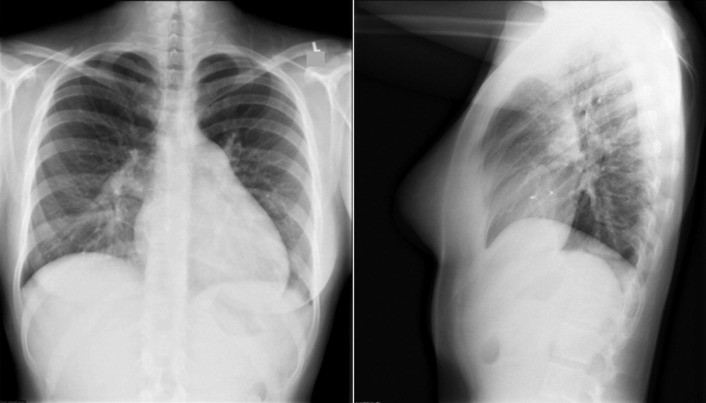

Left-to-right shunts initially result in volume overload of the chambers carrying the shunt volume, causing enlargement of the volume-overloaded chambers and an increase in pulmonary blood flow. If the amount of pulmonary blood flow is sufficiently high, obliterative disease of the pulmonary arterioles develops (“pulmonary vascular disease”), resulting in pulmonary hypertension. The chest radiographic appearance of pulmonary hypertension is one of centralization of pulmonary flow and accelerating enlargement of the right-sided chambers.

See Figures 18-5 to 18-31 . Possible findings are discussed in the following sections.